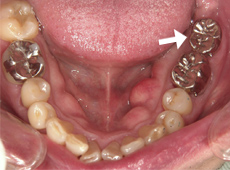

2.残っている奥歯は被せものが取れてしまっています。矢印の部位に親知らずを移植します。

4.親知らず(矢印)を移植した直後です。手前の仮歯と専用の接着剤で固定しました。